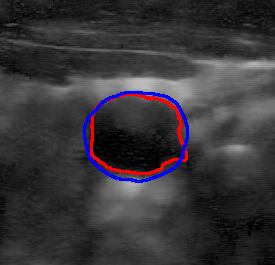

4.7 Downstream Task on Ultrasound Image Segmentation

To showcase the potential of the proposed denoising method quantitatively for ultrasound image understanding, we evaluate its impact on carotid ultrasound segmentation as a downstream task [9]. In this task, we use unseen noisy carotid images collected from the Clarius device. Then, unsupervised Segment Anything 2 (SAM2) [66] and the rule-based Flood Fill algorithm are used to extract the carotid artery from noisy and denoised images processed by various despeckling algorithms. In both cases, we place the seed point at the geometric center of the carotid lumen in each frame.

The quantitative result in terms of both IoU and AUC has been summarized in Table 6. To provide an intuitive visualization of the comparison, the results of SAM2 on a representative image and its denoised variants are presented in Fig. 12. It can be seen from Table 6 that the overall results using SAM2 are significantly improved in comparison to the Folld fill algorithm. This is primarily because of the strong generalization capability of the foundation model itself. Although the results produced by SAM2 across different images are comparable, the outcomes on images denoised by our method consistently demonstrate superior performance. The AUC reaches the highest score among all methods, while the IoU achieves the second-best performance. This performance advantage becomes more pronounced when using traditional region-growing algorithms such as the Flood Fill method. Significant improvements in both AUC ( vs ) and IoU ( vs ) are observed when applying the proposed Speckle2Self denoising approach.